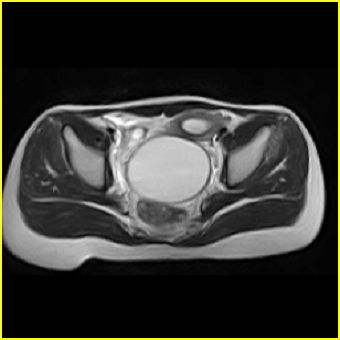

女、15岁、下腹疼痛2天,排尿困难1天。查体:处女膜闭锁,距处女膜约4至5cm处扪及一约5cm直径的圆形包块,张力较高,触痛明显、欠活动。b超提示子宫增大伴宫内增强回声团。

影像意见:子宫直肠陷凹积血。

更正影像意见:阴道积血。

处女膜闭锁,阴道积血

处女膜闭锁,阴道积血,子宫积血.

阴道积血,子宫积血.

子宫及阴道积血。

处女膜闭锁,伴子宫及阴道积血.